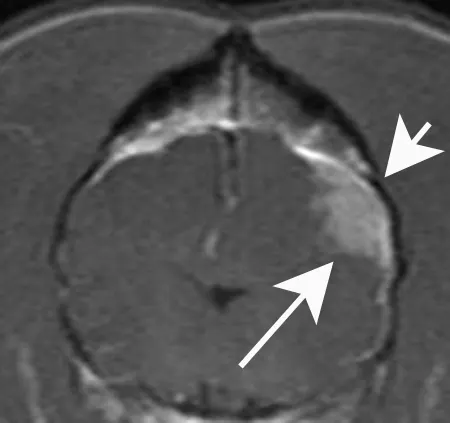

A transverse postcontrast T1- weighted MRI of the brain of a dog with a meningioma that caused seizures. The tumor is clearly evident as a homogeneously enhancing mass (long arrow). Note that the skull directly over the mass is increased in thickness (short arrow), a common finding with meningiomas.